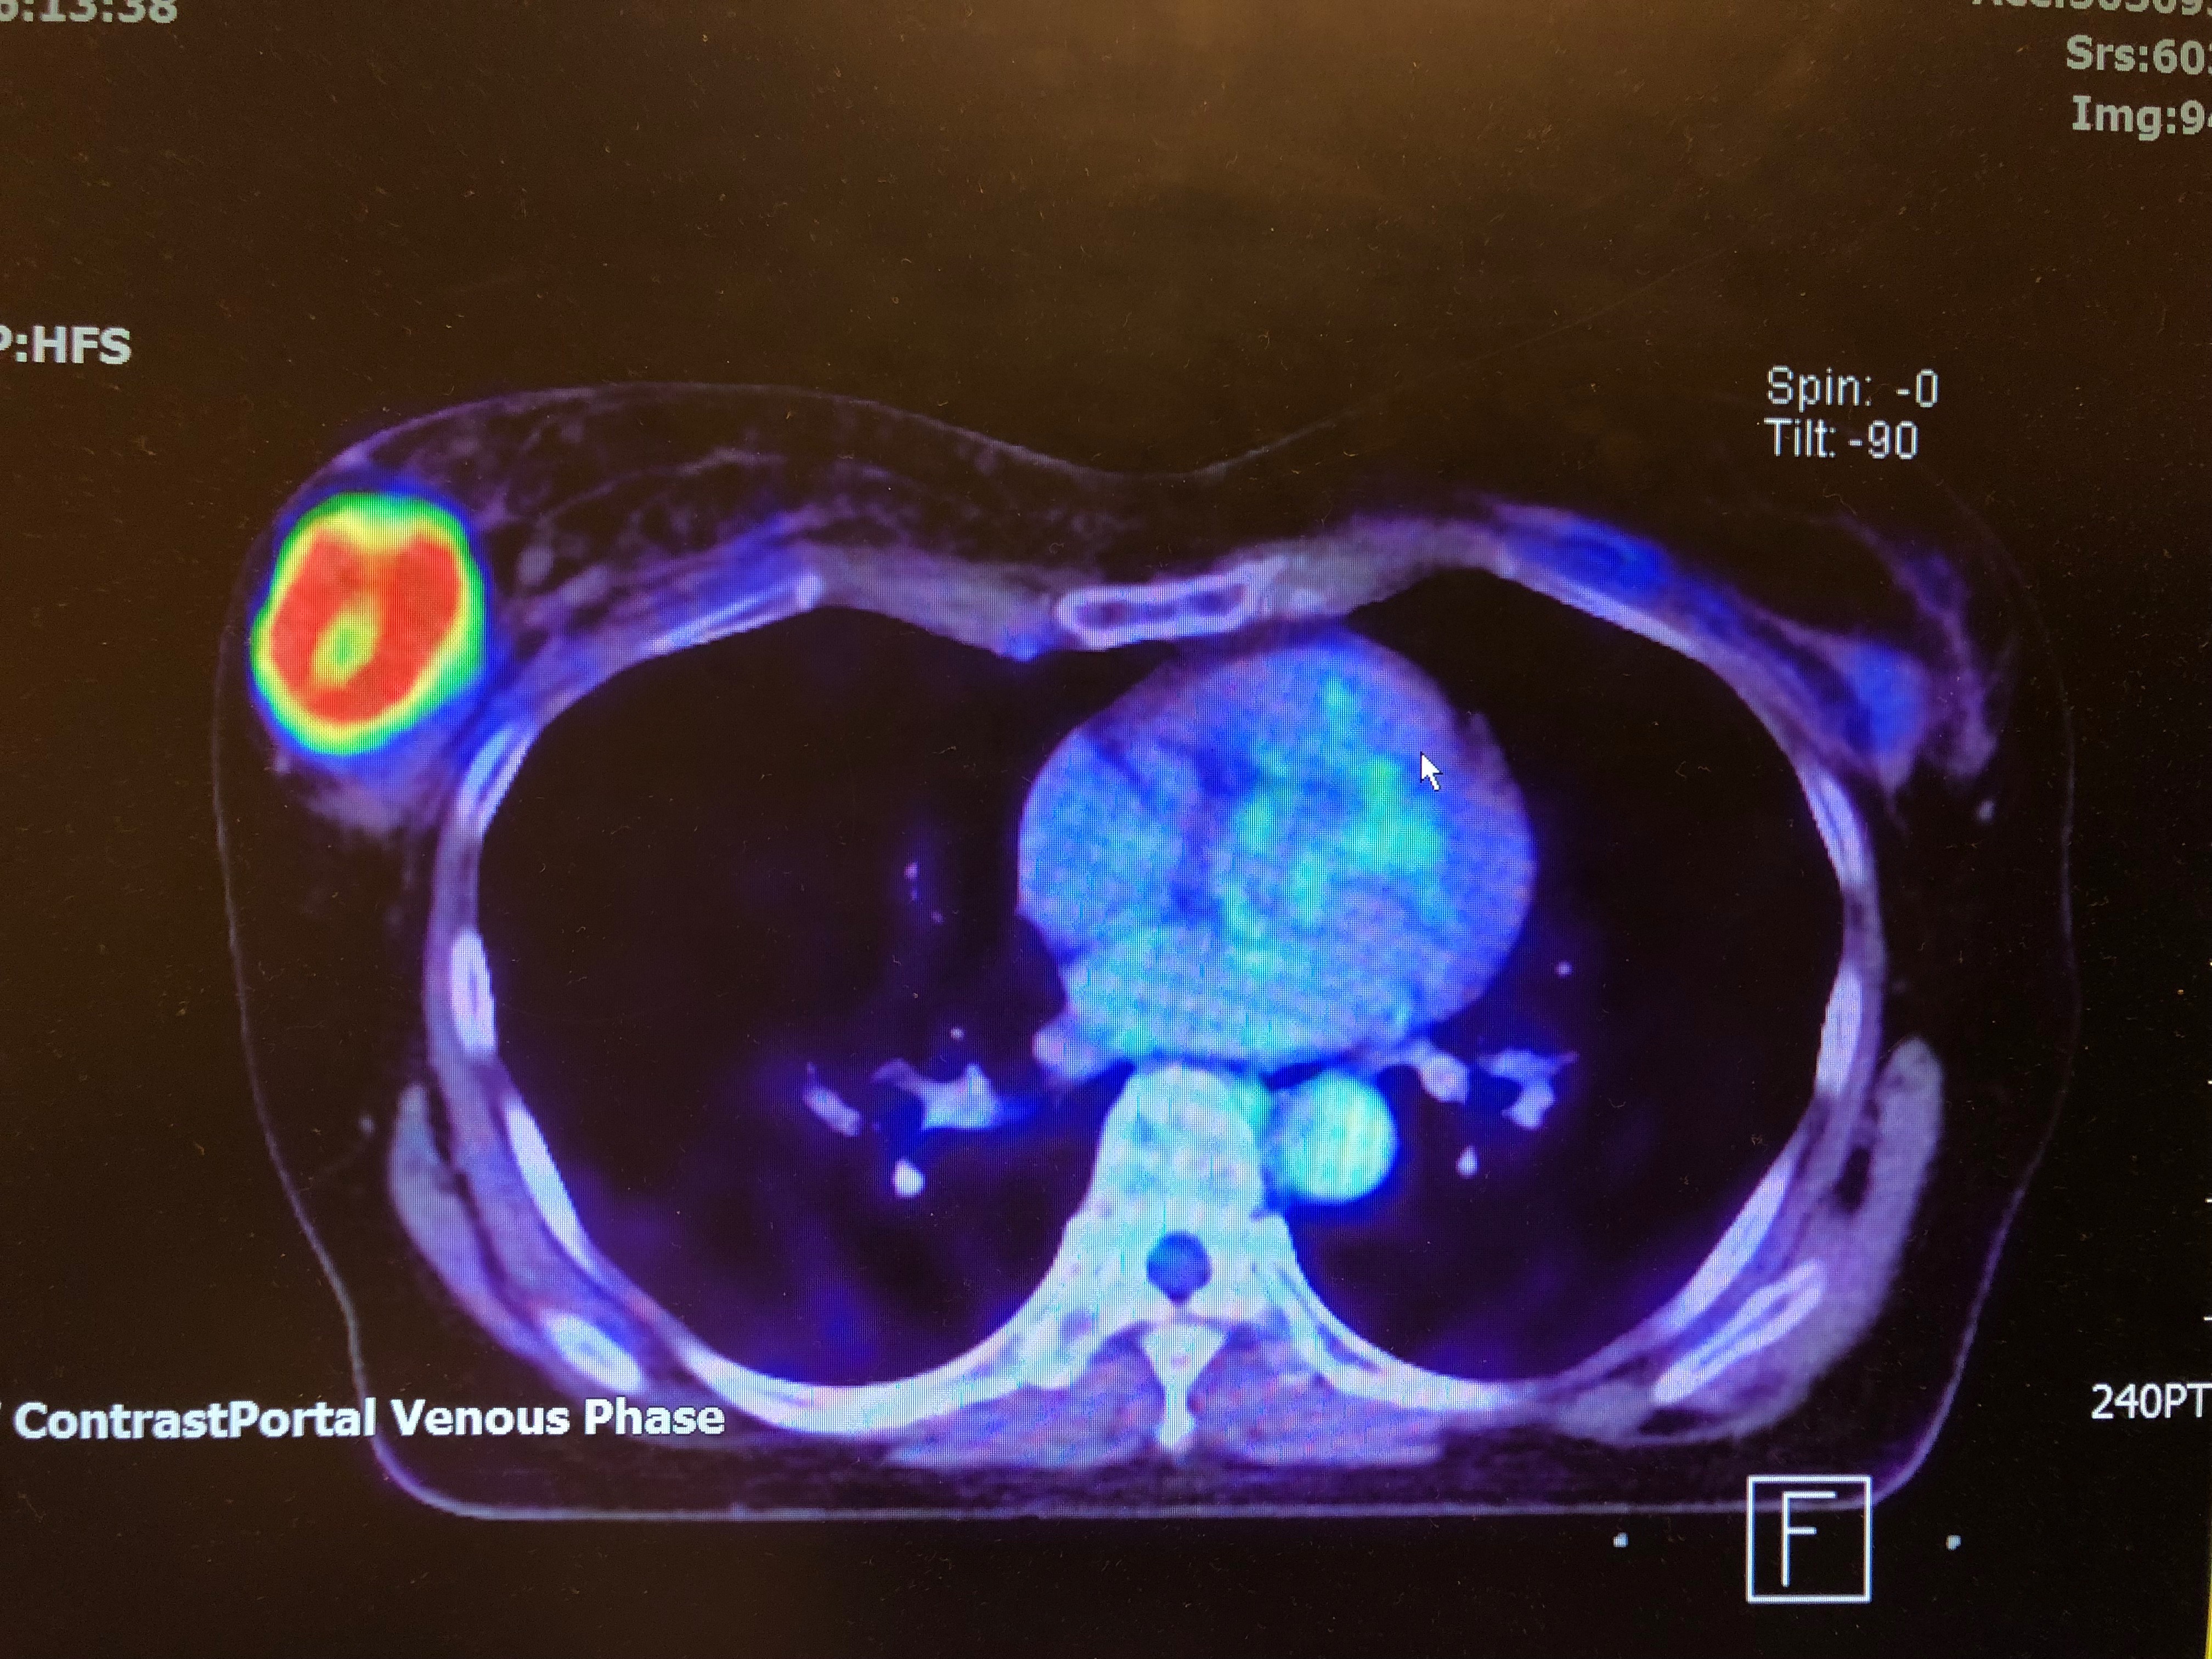

PET /CT Scan (Positron Emission Tomography)

A special radioactive sugar is injected into the vein and travels throughout the body. Cancer cells will absorb the high amount of radioactive sugar and scan picture taken will show where the cancer is collected. It is a very expensive investigation but sensitive to detect cancer cells